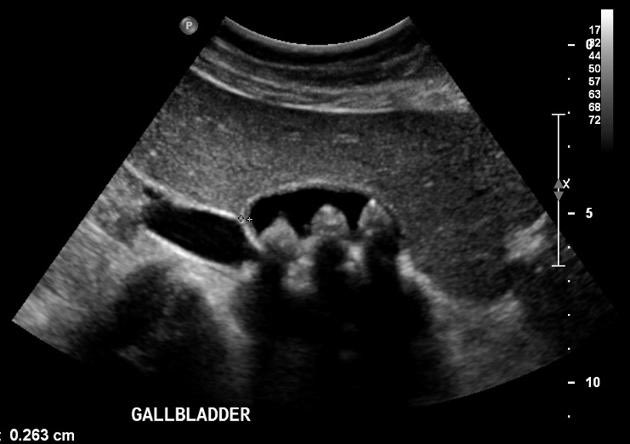

تشخيصها: عن طريق الموجات الصوتية المرارة و الكبد (الصونار) و الرنين المغناطيسي. الاشعة المقطعية فقط في حصوات الكالسيوم.

في الغالب لا توجد اعراض لحصوات المرارة انما يتم اكتشافها بمحض الصدفة اثناء اجراء موجات صوتية او رنين مغناطيسي لمنطقة البطن لاسباب اخرى. و تتفاوت اعداد و احجام الحصوات مما يتناسب طرديا مع وجود الاعراض و حدتها.